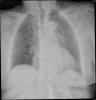

Fibrosis pulmonar. ICC.

Neumonia basal derecha.

Neumonía basal derecha.

EAP